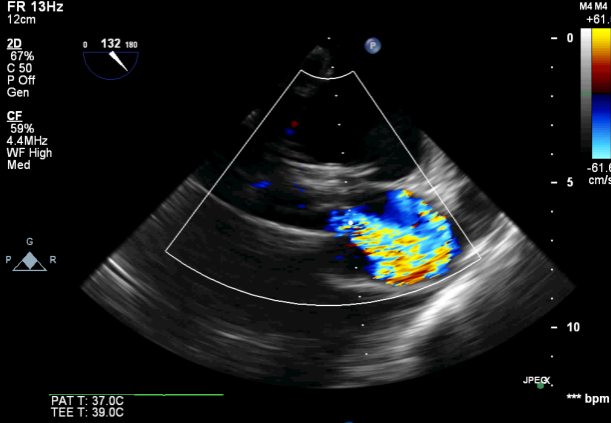

图6.TEE提示未见瓣周漏,CW示过瓣流速较术前明显下降